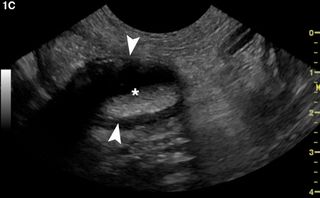

Fetch San Diego keynote speaker Dr Mariana Pardo breaks down performing ultrasounds to encourage their use on each patient